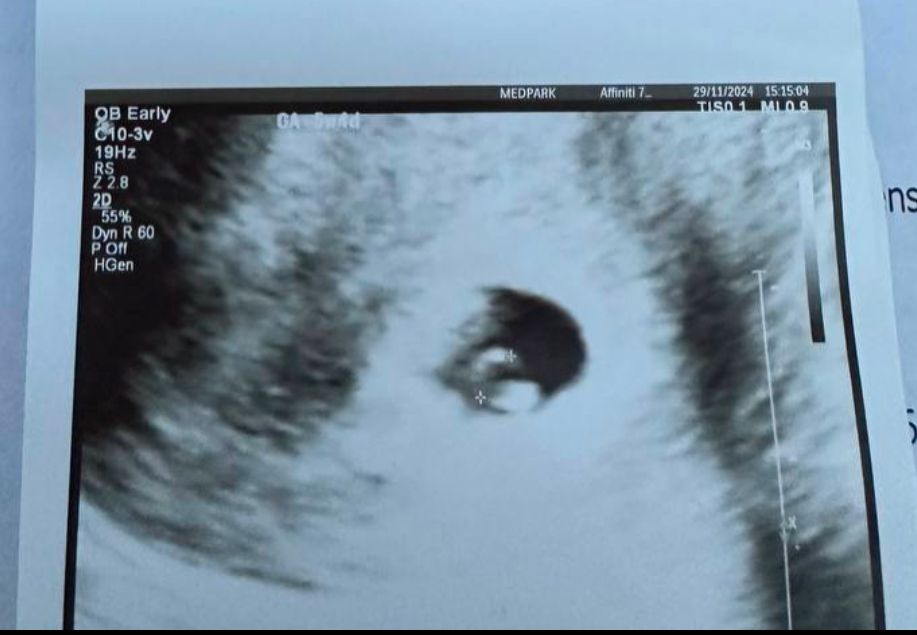

Julia

Лёвушка, вот мое узи с ктр 2.5. На фото как раз замерян ктр, а ниже - ЖМ. Как видите, оно на этих сроках супер нечеткое все)